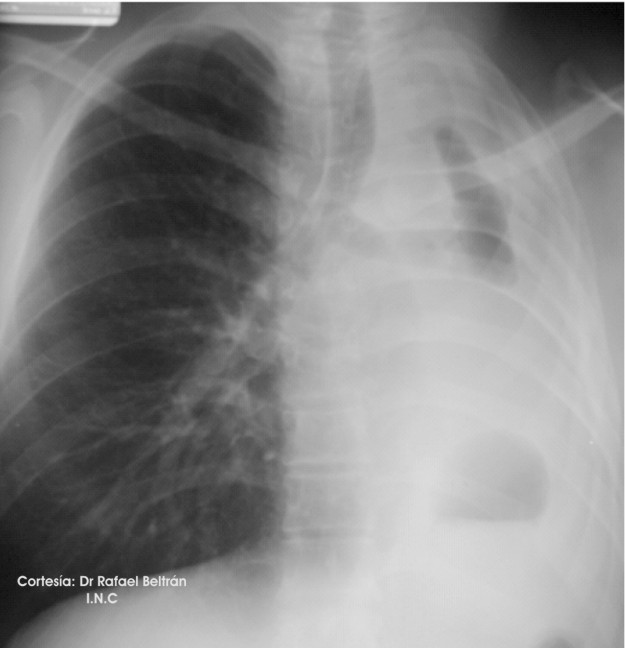

Rx Preoperatoria: Llama la atención la desviación traqueal. lo cual puede dificultar la posición correcta del tubo,

especualmente el Robertshaw derecho